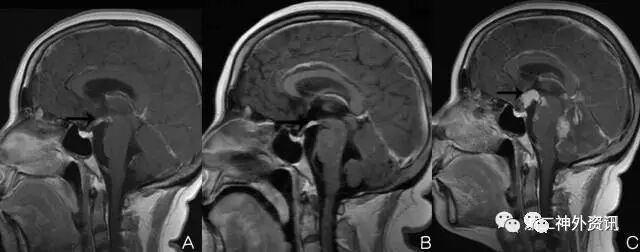

但患者V-P分流术后5月,因再次症状加重复诊,经检查提示颅内多发病灶以及脑膜强化。立体定向活检后证实为多发转移性肿瘤。回顾复习以前的MRI检查,发现早期在垂体柄漏斗部软膜已有转移,之后逐渐明显(图9)。说明该病例首次表现出来的颅高压是转移性肿瘤软脑膜转移为主的“脑膜癌病”所致。之后病情进展,演变为软脑膜转移和脑实质内多发转移共存的混合转移灶。

图9. MRI检查演变过程,A:首次MRI强化检查,见垂体柄漏斗部小片状强化,B:第二次检查片状强化较第一次明显,C:上述部位及整个脑干腹侧面大片软脑膜强化